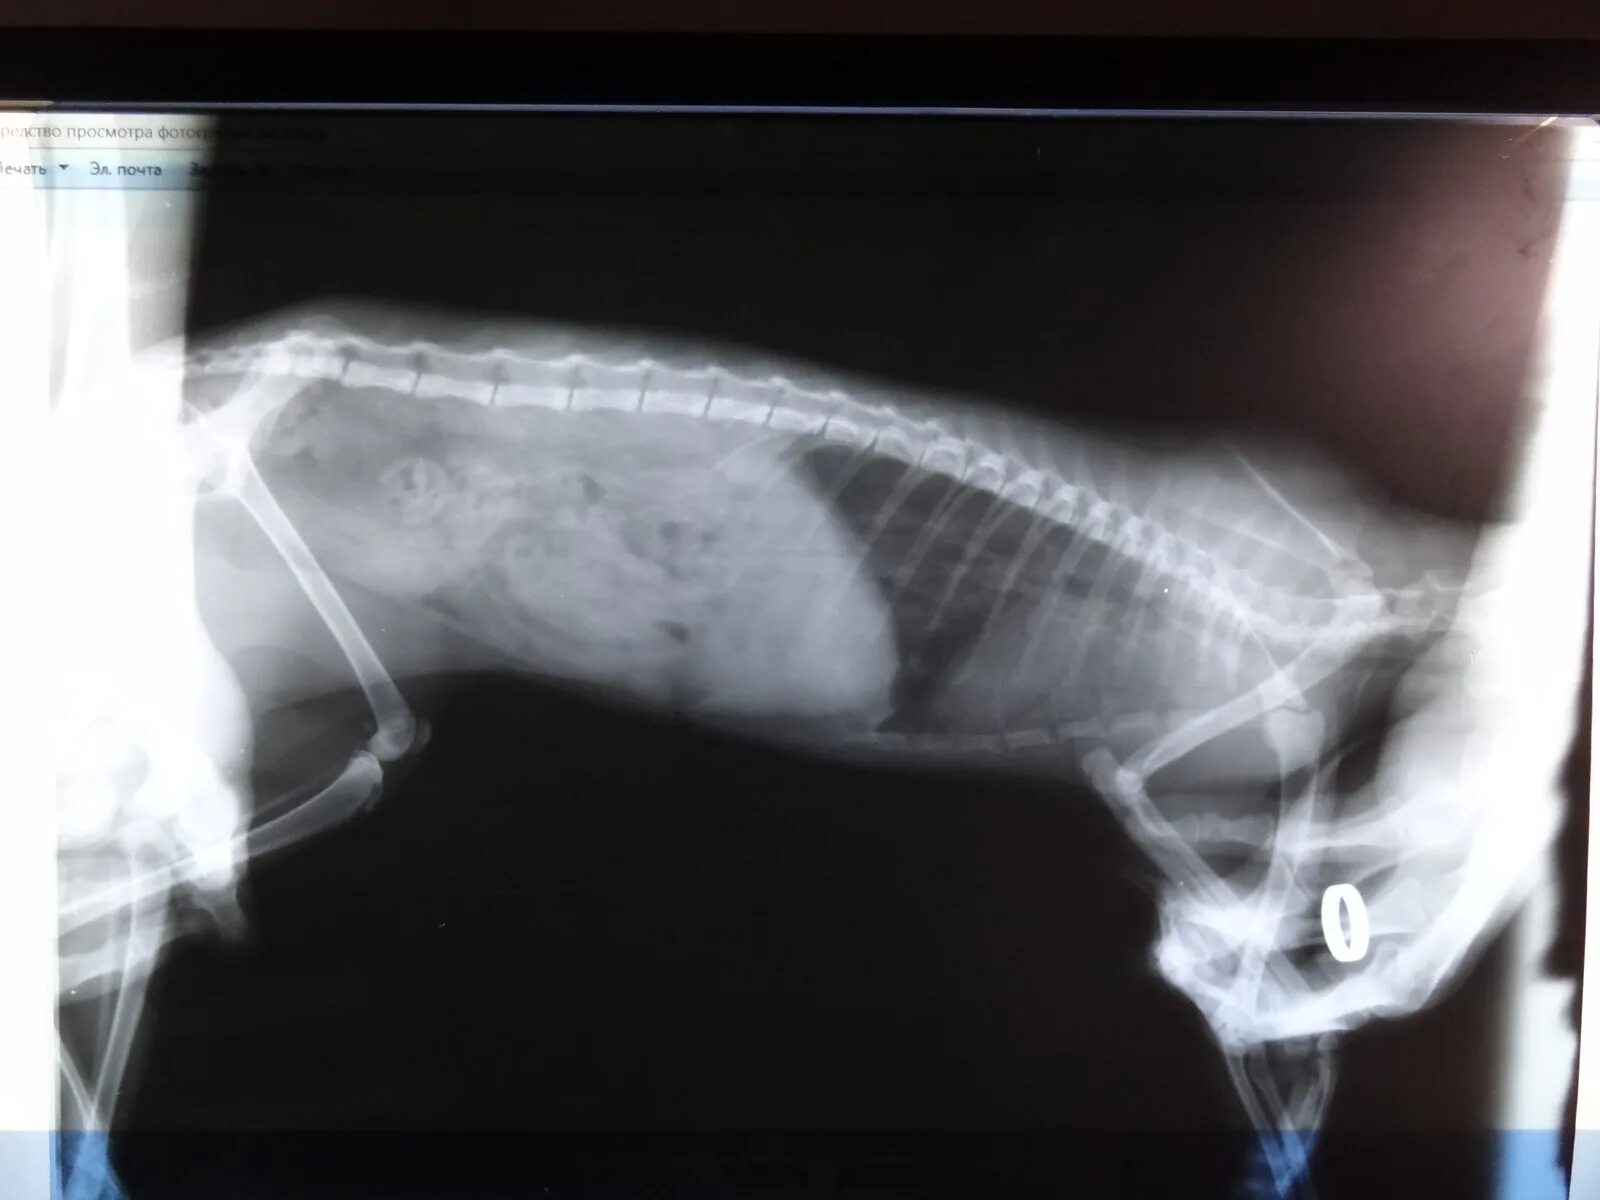

Астма у кота